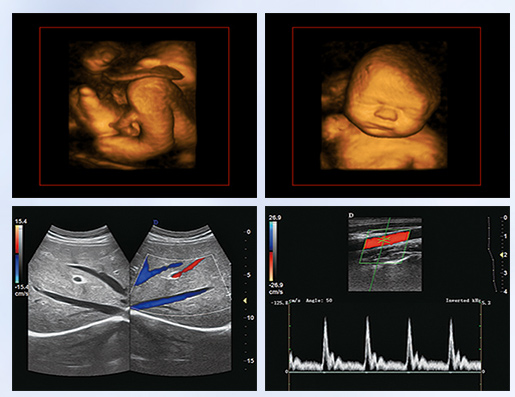

超聲學(xué)科的發(fā)展史,猶如一卷悠遠(yuǎn)綿長的畫冊。從黑白B超機(jī)到彩超機(jī),從一維、二維向三維立體動態(tài),從推車式B超機(jī)到便攜式彩超機(jī),從觀察人體解剖學(xué)到分析人體組織內(nèi)細(xì)微結(jié)構(gòu)和功能。隨著科學(xué)技術(shù)的不斷發(fā)展,B超機(jī)功能也越來越方便強(qiáng)大。

超聲作為一門醫(yī)、理、工相結(jié)合的學(xué)科,涵蓋超聲診斷、超聲治療和超聲工程技術(shù)等門類,其在臨床診斷和治療中發(fā)揮著日益重要的作用。B超機(jī)借助各種超聲探頭,以精湛的技術(shù)和嚴(yán)謹(jǐn)?shù)膽B(tài)度掃描著人體臟器內(nèi)的細(xì)微病變,給臨床提供準(zhǔn)確而快捷的檢查報告,在影影綽綽間,發(fā)現(xiàn)病魔的蛛絲馬跡中,用“金睛火眼”挽救患者性命……超聲的每一幅圖像,都是靠超聲醫(yī)生親自探查并采集的,每一個患者,至少都有10張以上的圖像存儲,對于比較復(fù)雜的病例,有幾十甚至上百張。而且所有的圖像,都需要超聲醫(yī)生在邊探查的時候,邊思考分析。這,是一個真正手腦并用的工作。